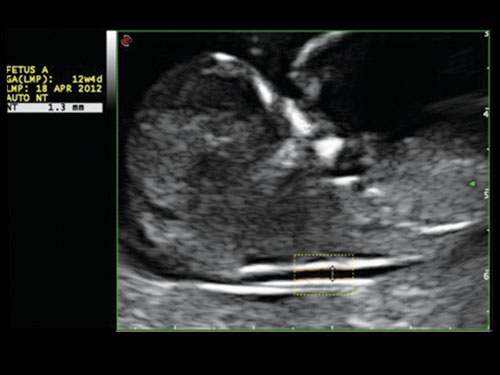

AutoNT: Automatické měření nuchální translucence (NT).